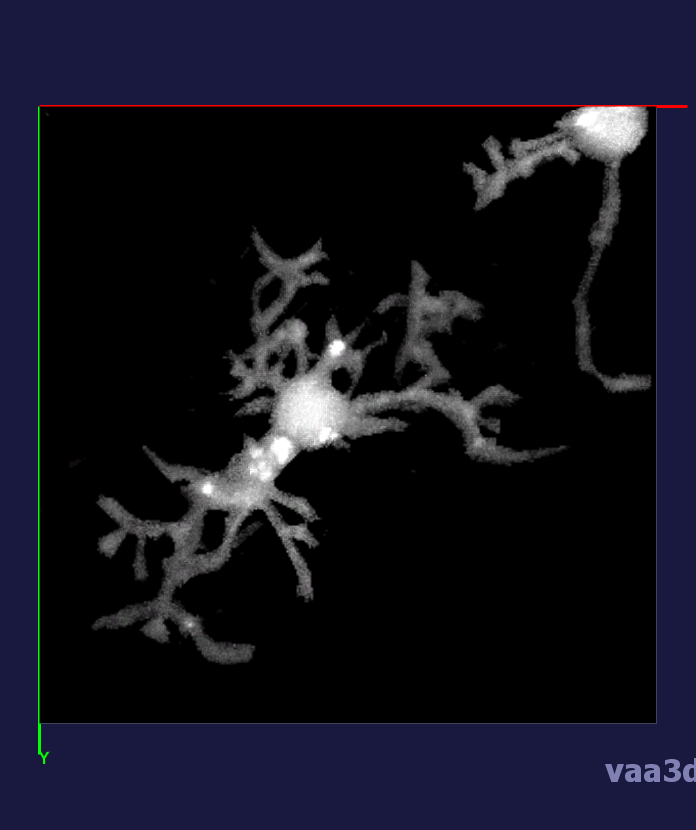

In our experiments, we compare the coupled TuFF-BFF microglia segmentation results with those given by L2S [21] and the Chan-Vese segmentation method [22]. The groundtruth in 3D was attained by manually tracing the object slice by slice from the z-stack. It must be noted that this was done by eye and could have some error. Figure 2 shows the visual comparison of the segmentation results for our dataset. Our result shown on the third column captures both the soma and processes. Figure 3 shows the Dice coefficient comparison of each segmentation method to the ground truth. Since the soma is much larger than the fine processes in the microglia, the processes have less volumetric impact on the similarity score. As explained in Section 1, segmenting the processes is important for quantifying the extension from the soma and its volume of surveillance. We use the Dice coefficient to quantitatively compare the ramification by taking the convex hull of the resulting segmentation. The Dice coefficient is a similarity measure that is computed using with where is the ground truth and is the compared image.

From Figure 4, the average Dice score for coupled TuFF-BFF was 0.77, compared to 0.53 for L2S [21] and .58 for Chan-Vese [22]. It must be noted that L2S required manual user initialization for each 2D image in the stack. While the Chan-Vese method has automatic seed selection, our coupled TuFF/BFF method was the only method that was a true 3D segmentation algorithm. L2S could not consistently capture the entire processes due to the intensity inhomogeneity throughout the object and background noise. The Chan-Vese segmentation could capture the extensions of the processes but did not work well with noise and attained false positives in the reconstruction. Since our method uses the tubular and blob information of the object to separate foreground and background, the segmentation only evolved within the object boundaries.